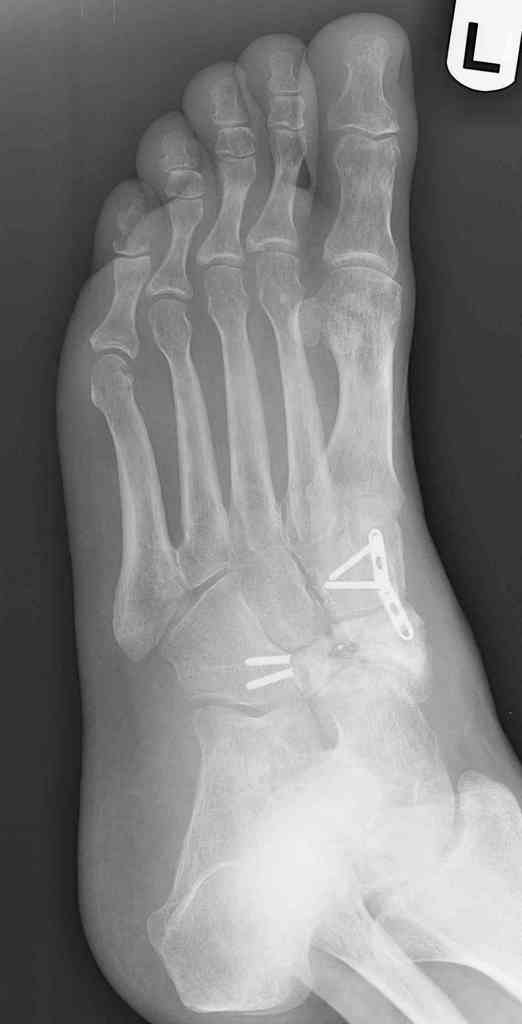

Navicular non-union

This is a 44 year old male laborer, smoker, who had his foot caught in a forklift about a year ago.

He had an ORIF and subsequent removal of hardware and presented to me with severe midfoot pain. His medial column is grossly unstable on exam but is passively correctable. Wounds are well healed, no sign of infection.

I haven't found much literature on salvage for this. What next? Iliac crest graft for structure with talo-navicular-cuneiform arthrodesis to restore the medial column? Will this fuse as an isolated procedure and given the loss of most of his subtalar motion, would a talocalcaneal arthrodesis improve his chances of fusion?